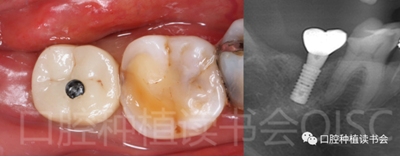

5.3.9 術(shù)后第6周,47行種植2期手術(shù),可見種植體周圍愈合良好,牙齦成型后,旋入愈合基臺(圖22)。

圖22 種植體周圍獲得了良好的骨整合。

5.4.1 術(shù)后第8周,47取種植開窗式印模,O-Bite記錄咬合關(guān)系(圖23)。

5.4.2 47選擇原廠CAD/CAM基臺+ 愛爾創(chuàng)“魅影”全鋯冠,口外粘接為一體冠(圖24)。(義齒加工單位:哈爾濱芽美美牙工作室)

5.4.3 術(shù)后第10周,47戴入最終種植冠,X片確認(rèn)基臺就位準(zhǔn)確(圖25),以30N.cm扭矩旋緊基臺螺絲(圖26)。

5.4.4 種植冠封閉螺絲孔后,調(diào)合,拋光,完成最終修復(fù)(圖27);戴牙前CBCT顯示:種植體頰側(cè)骨板厚度為2.88mm;47種植冠獲得了良好的穿齦輪廓,并維持了正常的頰側(cè)牙弓輪廓。